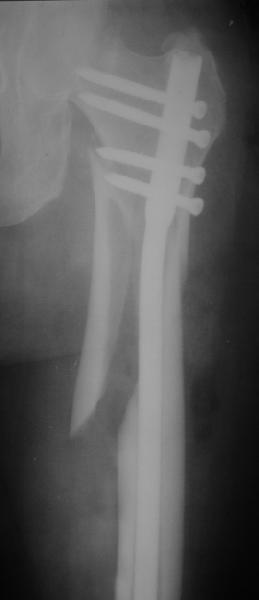

При межвертельных переломах с цефаломедуллярными гвоздями бывает, что проксимальый винт проходит или черед периферический отломок, или прямо над ним. И если остался диастаз, то этот винт при осевой нагрузке не дает сблизиться отломкам. Пример такого остеосинтеза в застарелом случае в приложении.

В качестве предупреждающей меры можно долотом разрушить латеральную стенку дистального отломка под винтом.

В частности, на проксимальном конце сделано еще одно дополнительное статическое отверстие. Можно ввести в проксимальном отделе 4 винта, из них 3 статические (2 в круглые отверстия и 1 по нижнему краю овального). Картинки в приложении. На дистальном конце стержня тоже кое-что улучшено. Спрашивайте в аптеках, как говорится. Выпускается предприятием "ЦИТО" (Москва), то есть это малобюджетное решение.

Конечно, мы не синтезируем остеопорозые вертельные переломы согласно прилагаемому примеру, винты 6 мм вырежутся. Но у более молодых при хорошем качестве кости такие или подобные гвозди с поперечным расположением винтов вполне применимы для меж- и подвертельных переломов.

Это было года 2,5 назад, мы тогда еще уточняли возможности шинирования с угловой стабильностью гвоздем с поперечным расположением винтов при переломах проксимального отдела бедра. Пациенту не пришлось приобретать намного более дорогой рекон или проксимальный гвоздь. В приложении еще несколько примеров применения того гвоздя при высоких переломах бедра, в том числе с более латеральной точкой входа. Гвоздь изгибаем для этого.